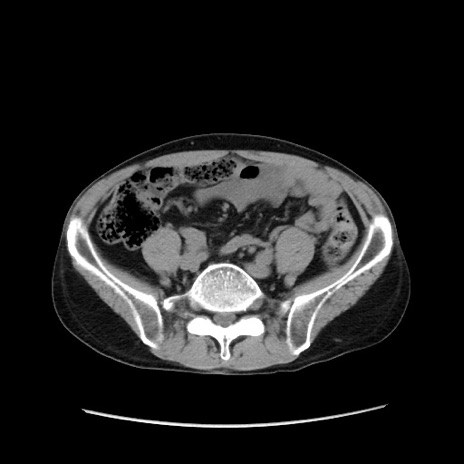

冠状断像